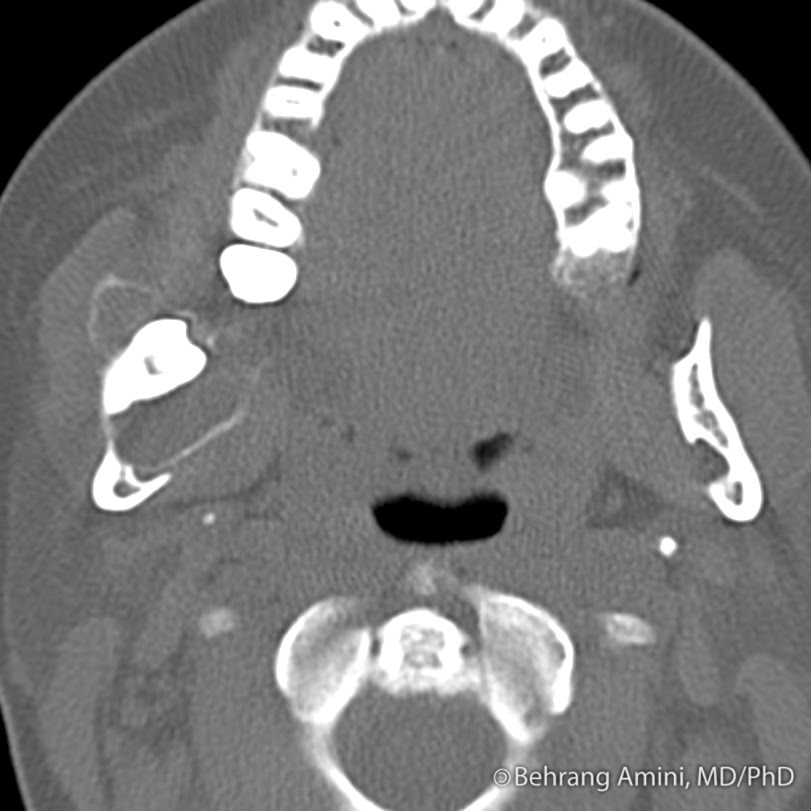

Radiological investigations. (A) CT scan of the face showing expansile